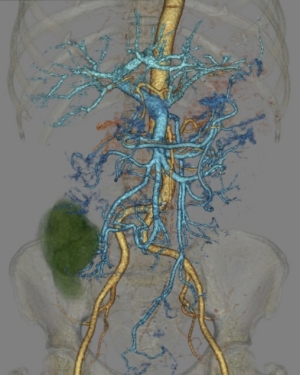

術前には造影剤を併用し、大腸、血管、腫瘍の画像をFusion(重ね合わせ)する事によって、術前シミュレーションを行う場合もあります。

手術支援

手術支援3D画像(腹部)